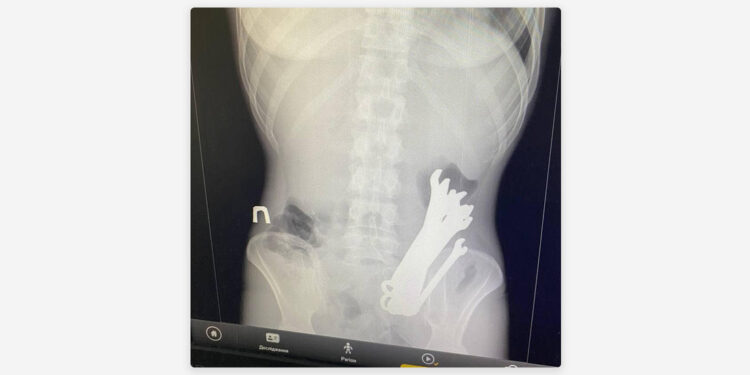

Una radiografía que le hicieron al hombre antes de la intervención reveló que dentro de su estómago se encontraban varios objetos de hierro. Durante la intervención quirúrgica, los médicos sacaron del estómago del hombre un total de seis llaves de tuercas.